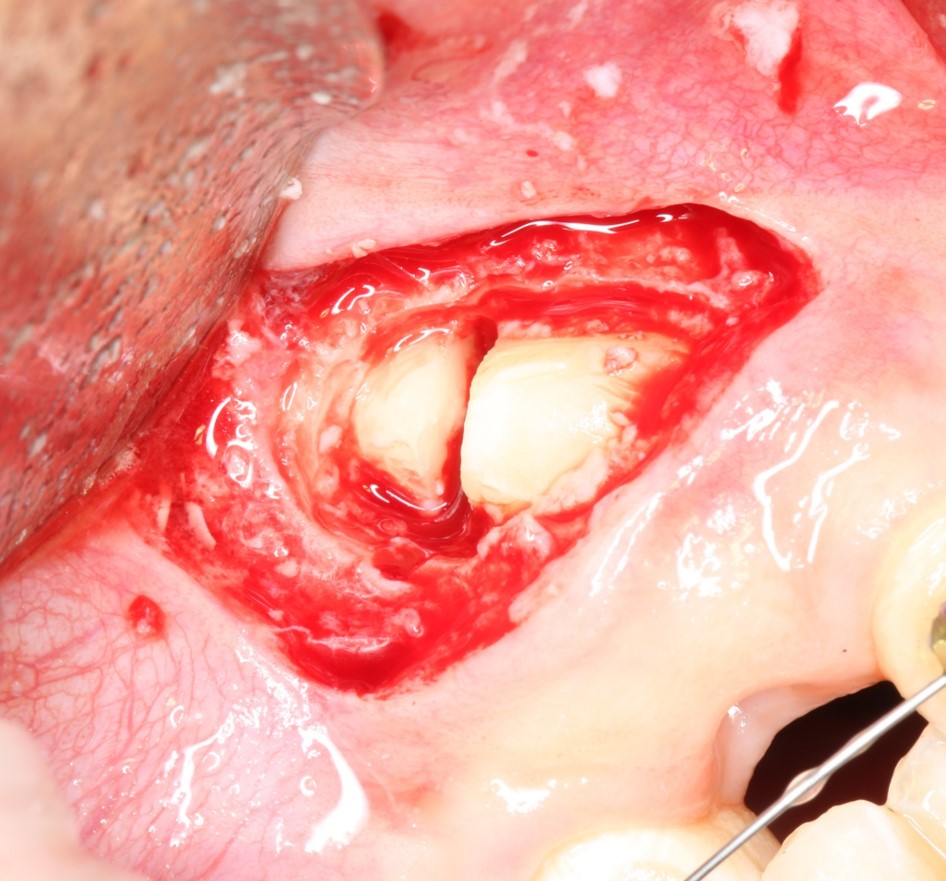

когда мы понимаем этот принцип, то удаление даже самых сложных зубов становится очень простым и безопасным занятием и занимает не более 15-20 минут. Как, например, в этом случае, мы удалили ретинированный клык минут за десять. Хотя, в другой клинике обещали операцию в несколько часов.

Другими словами, «страшная» форма зуба, кривой корень или «ненормальное» положение зуба не являются чем-то осложняющим процесс удаления. Любую «страшную форму» можно представить как совокупность нескольких «нестрашных» — и спокойно приступать к операции.

Конечно, мы можем удалить и зуб мудрости, и появившуюся из-за него фолликулярную кисту. Такая операция занимает, максимум, 20-25 минут:

Но по сложности это вмешательство выше, чем просто удаление ретинированного зуба, а по времени — дольше (удаление такого зуба, как на первом снимке, занимает 10-15 минут). Я уже не говорю о возможных рисках — несомненно, простое удаление ретинированного зуба мудрости более безопасно, нежели удаление ретинированного зуба с развившейся фолликулярной кистой.

Следовательно, удали мы этот зуб мудрости раньше — меньше было бы возни, меньше проблем во время и дискомфорта после операции.